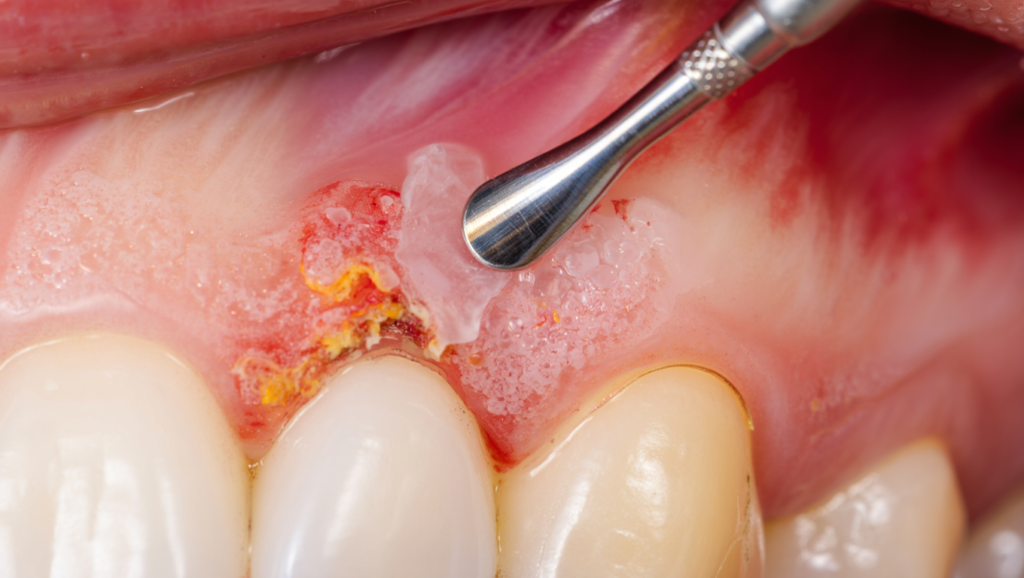

🔹 Bước 3: Làm sạch túi nha chu dưới nướu

✔️ Làm sạch túi nha chu

✔️ Hạn chế xâm lấn

✔️ Không làm tổn thương mô lành